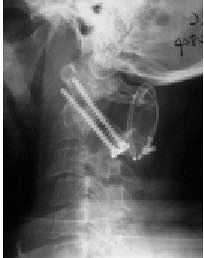

![]() |

FIGURE 11-12. Lateral flexion (A) extension (B) cervical radiographs demonstrating instability at the C1-C2 junction.